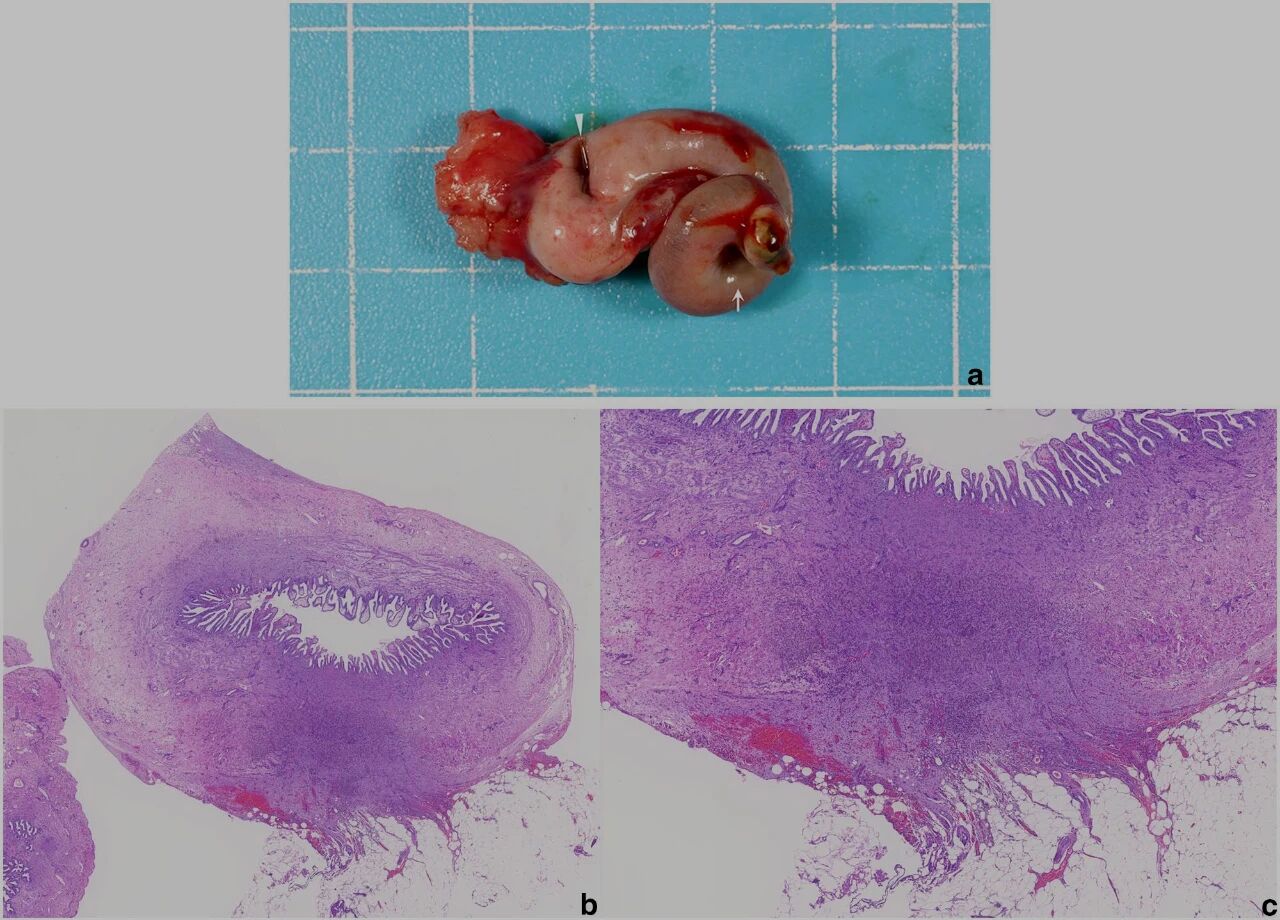

术中发现胆囊体部(胆管远端)发生四重扭转,未见肝叶扭转。胆囊底与大网膜粘连,未见胆囊破裂、腹水或色泽改变(下图)。用钳夹牵引胆囊,于扭转处近端胆管行结扎切断术后摘除胆囊。术中同时行肝活检。

↑ 术中照片。(a) 胆囊扭转,从颈部到体部观察到四重旋转。(b) 大网膜脂肪附着于胆囊底部。(c) 肝叶无扭转的证据。(d) 牵拉胆囊底部揭示扭转部位。靠近近端胆管处未见扭转(箭头)。

切除的胆囊呈现萎缩状态,从胆囊体部至颈部可见螺旋状形态。胆囊切除术后收集的胆汁经培养检测结果为阴性。病理学检查显示胆囊形态畸形,平滑肌层变薄,结缔组织水肿,黏膜上皮组织紊乱。大网膜粘连处可见肉芽组织及含血红素的巨噬细胞,胆管周围存在扩张的淋巴管。肝脏组织学检查显示肝细胞结构完整,未见显著异常(下图)。

↑ (a) 切除的胆囊显示出螺旋形态和萎缩。颈部显示轻微绿色变色(箭头)。(bc) 胆囊壁在粘连部位的组织病理,伴有肉芽组织和含血色素的巨噬细胞。